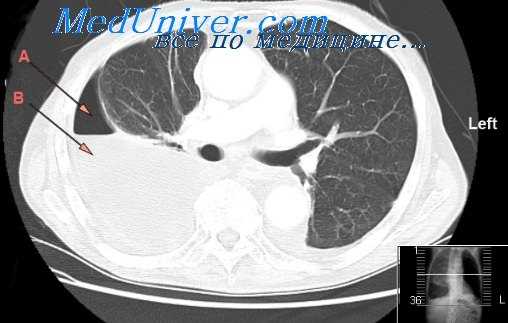

- Рентген. Полипозиционная рентгенография и рентгеноскопия легких при эмпиеме плевры обнаруживают интенсивное затенение. Для уточнения размеров, формы осумкованной эмпиемы плевры, наличия свищей выполняют плеврографию с введением водорастворимого контраста в плевральную полость. Для исключения деструктивных процессов в легких показано проведение КТ, МРТ легких.